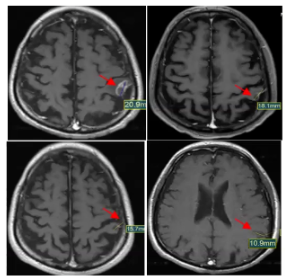

一位晚期肺癌脑转移的患者,脑部病灶已经有20.9mm大,基因检测存在KRAS g12c,接受最新国研药物D-1553治疗后,仅不到9周期,脑部的靶病灶就缩小了一半!

这款药物就是由益方生物自主开发的一款新型,高效口服的KRAS G12C抑制剂D-1553。最新的数据显示:接受各种剂量治疗的患者中,总客观缓解率(ORR )为37.8% (28/74) ,疾病控制率(DCR)高达91.9% (68/74)!这意味着超过90%的患者病灶有不同程度的缩小。